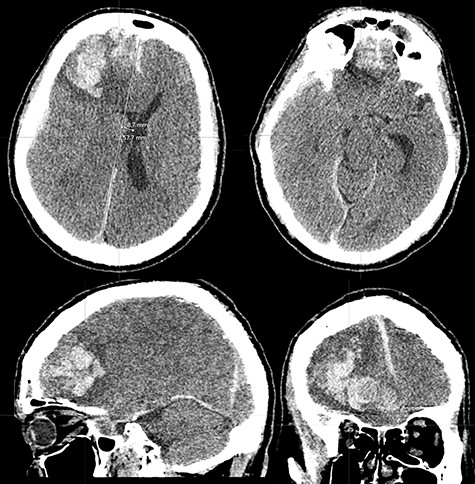

Initial assessment in the emergency room revealed a Glasgow Coma Scale (GCS) score of 11/15 (E1 V4 M6), equal and reactive pupils and a dense left hemiparesis—Medical Research Council Grade 1/5 power in both upper and lower limbs. His presenting blood pressure was 162/109 mmHg. He had been taking aspirin with prophylactic indication. Initial non-contrast computed tomography (CT) scan of the brain revealed a massive right frontal intracerebral hematoma with significant vasogenic edema and mass effect as shown in Figure 1.

CT brain scan showing massive right frontal ICH causing significant mass effect and transtentorial herniation (superior left and inferior right). There is also moderate vasogenic edema (superior and inferior left). The mass extends to the floor of the anterior cranial fossa (superior right and inferior left).